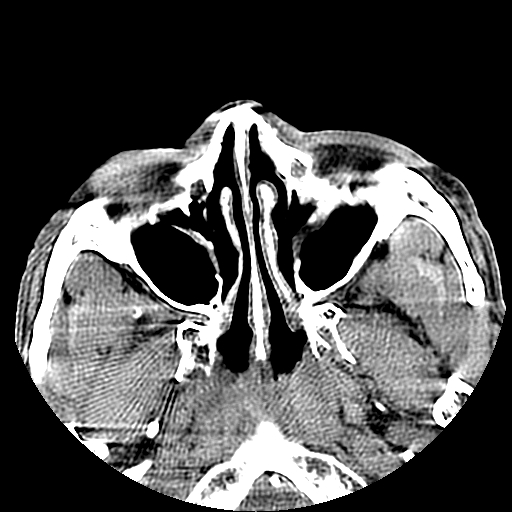

以下是引用liaoqiang在2008-7-16 21:15:00的发言:[br]右侧鼻骨骨折

以下是引用zxd95在2008-7-16 21:39:00的发言:[br]右侧上颌骨额突骨折。[br][br][br][br]